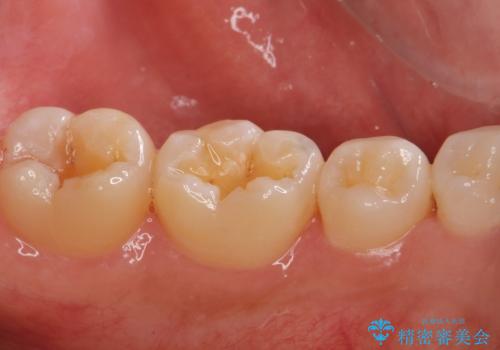

- 歯に穴が空いているとの事で来院。

セラミック、ゴールドの詰め物のご案内をしたところゴールドを希望されたのでゴールドインレーで治療を行いました。